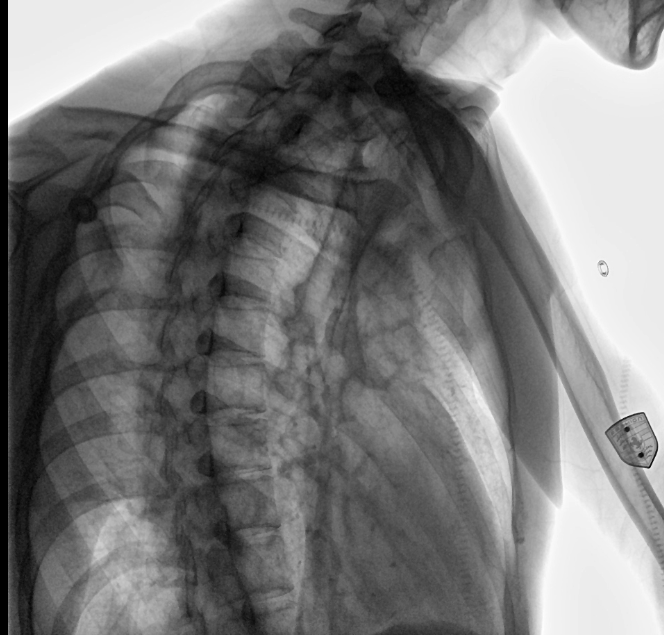

位于衡水市中醫(yī)醫(yī)院的動(dòng)態(tài)平板數(shù)字化X射線(xiàn)系統(tǒng)DTP571具備高速高清點(diǎn)片功能。這是一款對(duì)放射科十分友好的產(chǎn)品。因?yàn)樗迅咚俸透咔妩c(diǎn)片結(jié)合,既能方便影像技師有效地抓拍需要的病灶的影像,又能給予影像醫(yī)生清晰的影像進(jìn)行診斷

動(dòng)態(tài)觀察診斷,實(shí)時(shí)高清點(diǎn)片